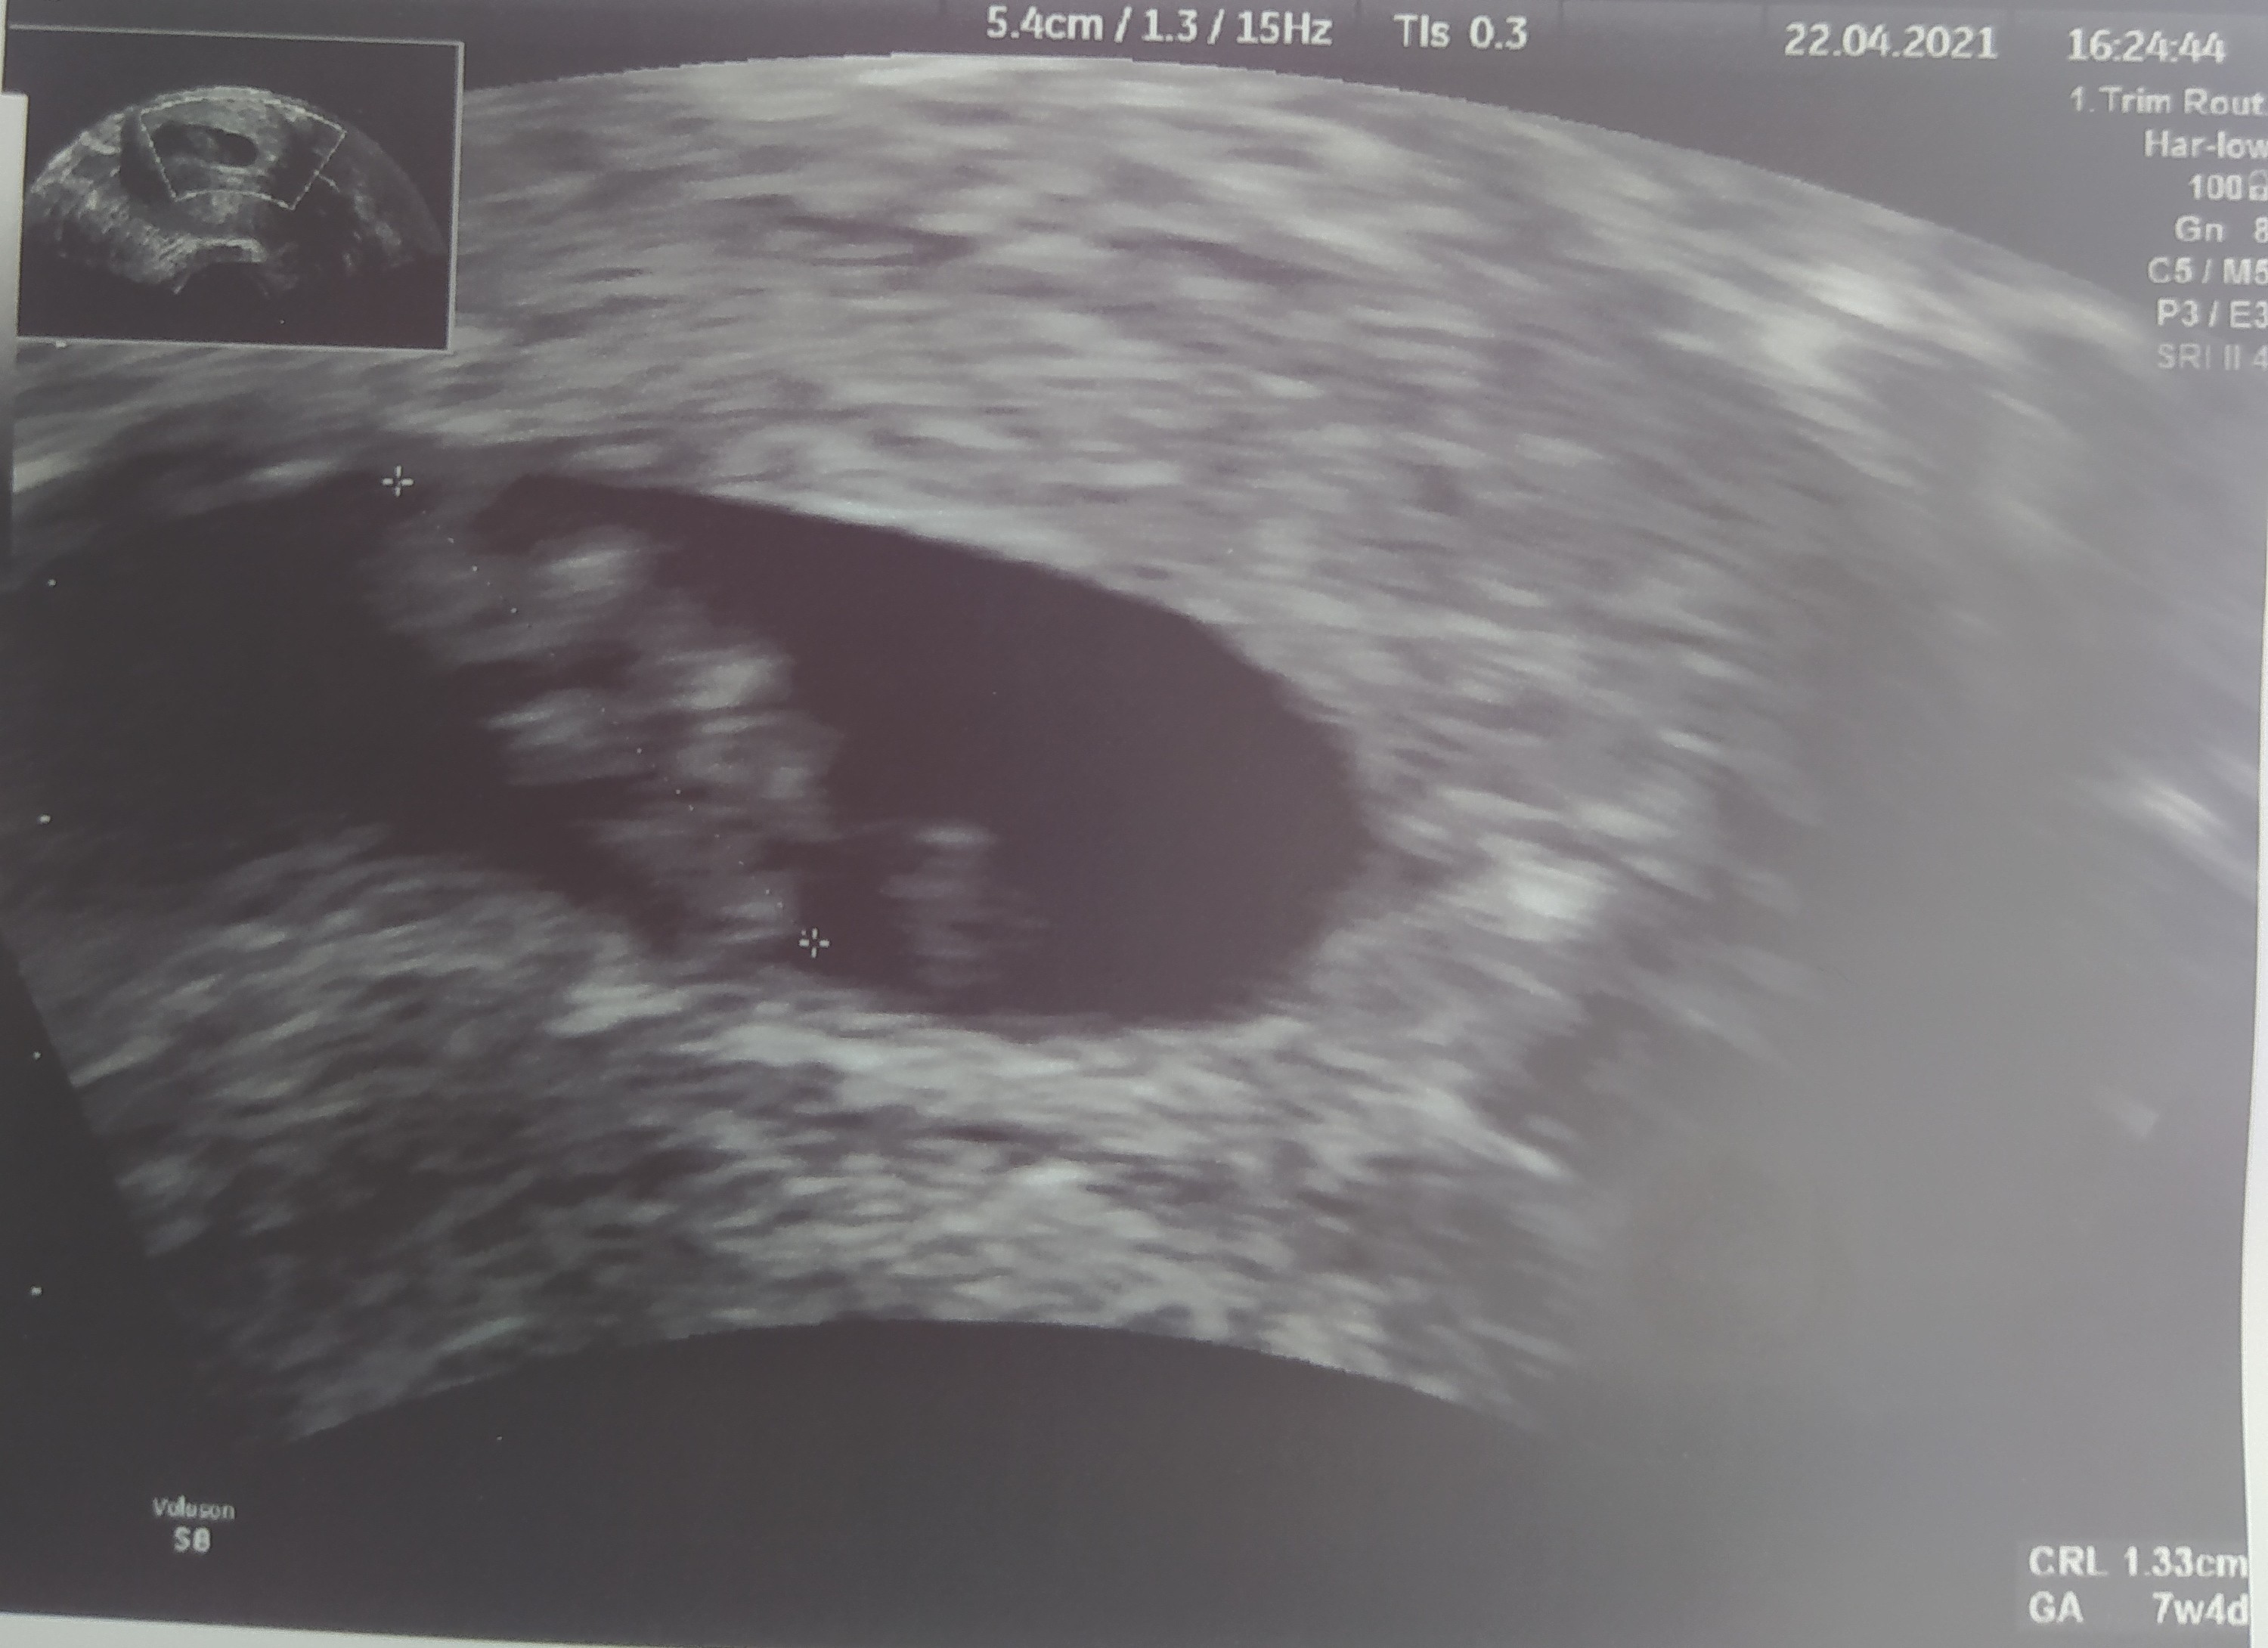

Nie za łączyło się zdjęcieJa też już po wizycie . Wszytsko w jak najlepszym porządku. Fasolka ma 1.33 cm wychodzi ze jest 7 tydzień 4 d. Serduszko ładnie bije. Karte ciąży założy mi dopiero na następnej wizycie. Jestem już troszkę spokojniejsza.